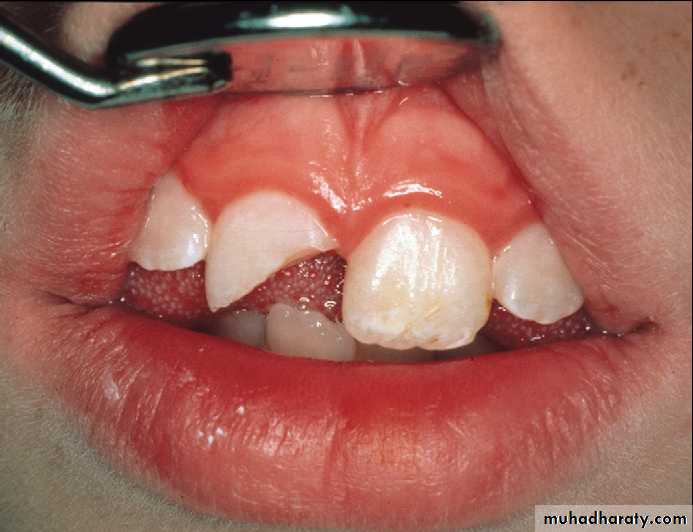

Crown-root fracture

Incisors with crown-root fractures